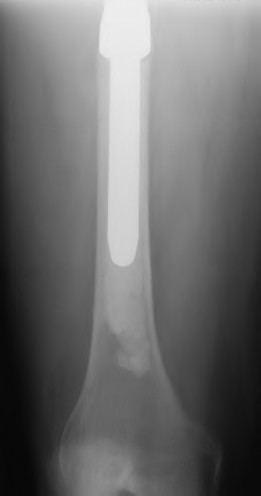

The radiograph demonstrates a periprosthetic femur fracture extending to the tip of the stem. The long spiral fracture is consistent with a loose implant. The bone stock is sufficient. Therefore, this fracture pattern would classify as a B2 using the Vancouver classification system. The Vancouver classification for periprosthetic femoral fractures is simple yet incorporates all the pertinent factors such a location, stem fixation, and bone stock. Type A is a trochanteric fracture- lesser or greater. These can be treated non-operatively usually and ORIF if symptomatic. Type B fractures are around or just below the stem and are subdivided into three types. Type B1 is a fracture with a well fixed stem.

The treatment is cable plating or allograft struts or a combination of the two. Type B2 is a fracture with a loose stem with good bone stock. The treatment is a cementless porous coated long stem atleast two diameter length past the

fracture site. Type B3 is a fracture with a loose stem and comminution. For younger patients, use cementless porous coated long stems with allograft struts. For older patients, consider a tumor prosthesis. Cement fixation is sometimes necessary Type C is a fracture well below the stem tip. These can be treated independently of the prosthesis.

A 72-year-old male presents 2 years status post fixation of an impending pathologic right femur fracture due to metastatic renal cell carcinoma. He is minimally ambulatory due to pain. Despite radiation therapy, there has been progression of the lesion with extensive cortical bone loss, which is shown in Figure A. A proximal femoral replacement arthroplasty is performed without complications, and is demonstrated in Figure B. Which of the following is true regarding this patients post-operative course?

Figure A shows a lytic lesion of the proximal femur with an intramedullary implant. Figure B shows a proximal femoral replacement.